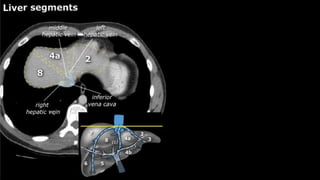

y is present, it is important to document its

location. This may be crucial to any surgical options. Using the

Couinaud classification, the liver is subdivided into eight individually

functioning segments. Each segment has its own afferent hepatic

artery and portal vein, and efferent hepatic vein and efferent bile

ducts

Liver segments Radiopaedia.com1

•Liver • A normalliver enhances homogeneously (irrespective of the scan phase). The liver receives about 80% of its blood through the portal vein (= nutrient-rich blood from the intestines). The remaining 20% is supplied by the hepatic artery. y is present, it is important to document its location. This may be crucial to any surgical options. Using the Couinaud classification, the liver is subdivided into eight individually functioning segments. Each segment has its own afferent hepatic artery and portal vein, and efferent hepatic vein and efferent bile ducts